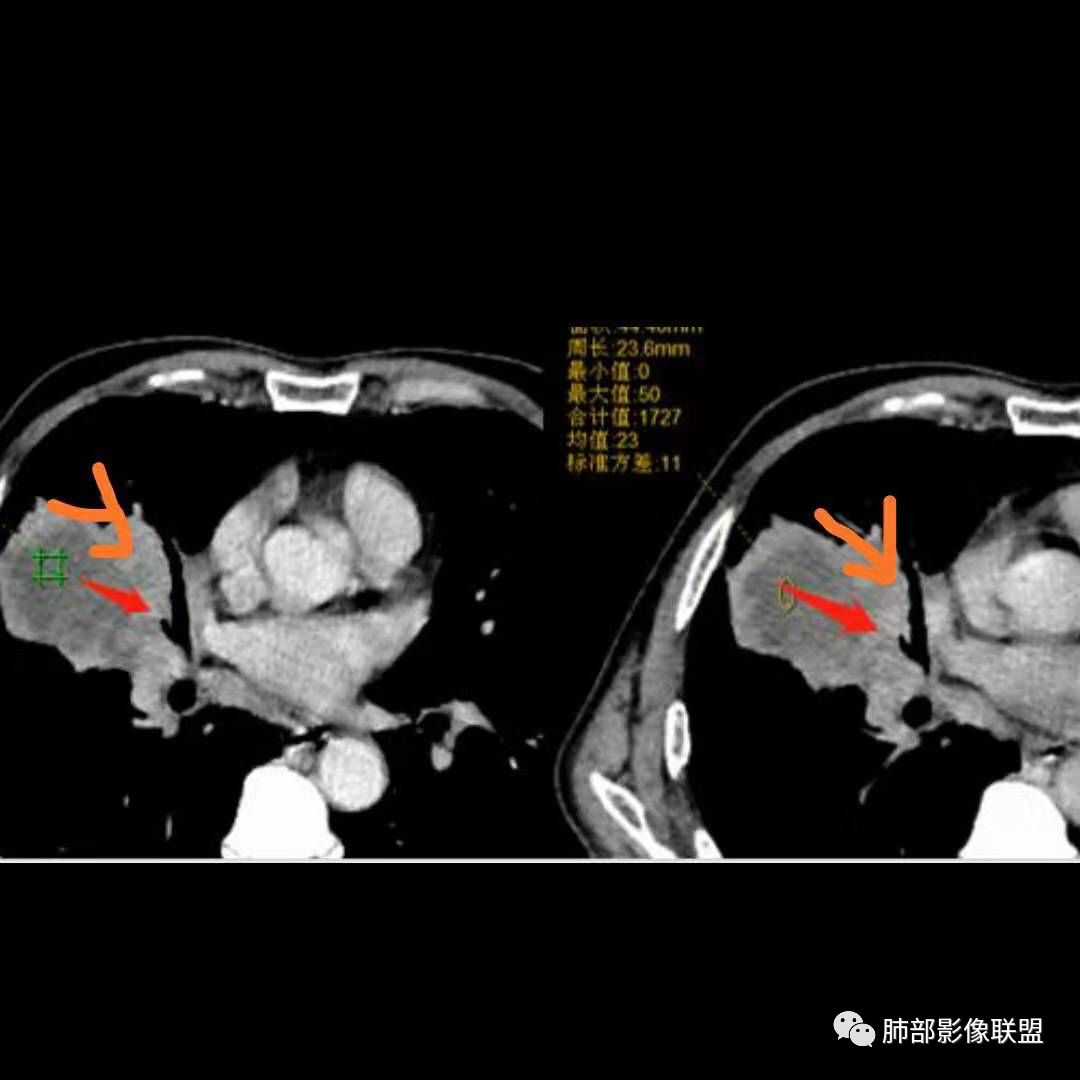

患者中老年男性,体检发现肺部占位。

胸CT:右肺中叶实性占位性病变,呈膨胀性生长,对斜裂明显挤压,右肺中叶外侧段阻塞,并在边缘可见分叶、毛刺、棘突样改变,胸膜牵拉;增强可见病灶明显强化,可见边缘模糊血管影,病灶内可见大片状低密度区,隆突下可见肿大淋巴结。

诊断考虑:恶性病变。

患者中老年男性,体检发现右肺占位。血常规轻度贫血,AFP、CEA正常,肝肾功能、血糖、血脂、心肌酶、电解质正常。胸部CT:右肺中叶巨大肿块灶,垮叶生长,可见分叶、毛刺、血管集束、支气管截断征象,远端周围可见小叶间隔增厚,增强轻度强化,内可见低密度坏死区,综合淋巴结肿大,且可见淋巴结内似低密度灶。综合考虑恶性,鳞癌并癌性淋巴管炎可能大。鉴别结核、腺癌。

胸CT:右肺中叶团块样实性占位,边缘膨隆,中叶外侧段阻塞,病灶可见深分叶、棘突,胸膜牵拉;增强不均匀强化,可见边缘模糊血管影,病灶内大片状低密度区,纵隔多发肿大淋巴结。

诊断考虑:恶性病变,鳞?大细胞?鉴别:TB

1.具有肉瘤的特性:肿瘤体积一般较大,直径约大于5cm,边缘清楚、光整,由于肿瘤生长迅速,可见大片坏死,坏死边界清楚;常见支气管推移。

2.具有癌些特性:如分叶、短毛刺、空洞,但是钙化及胸膜凹陷征少见,病灶往往是直接侵犯胸膜,可以远处转移,肺门及纵隔淋巴结可明显肿大;

3.强化方式:增强后病灶以环状强化为主,病灶周边多以癌组织为主,血供丰富,病灶中心区则以肉瘤成分为主,血供较差,易出现粘液样变性、坏死、出血,坏死边界清楚,所以增强CT对PSC与普通型肺癌有一定的鉴别价值。

1.本病例结合病理结果及影像综合分析,应该符合肉瘤样癌,上皮成分是腺癌为主;肿块的边缘毛刺、分叶及周围癌型淋巴管炎征象有符合腺癌的影像表现之处。

2.肿块巨大局部边缘膨隆、光整,坏死较彻底;明显跨叶生长(途经发育不全叶间裂或肺门,注意患者没有胸水),支气管阻塞伴推移等,这些更符合肉瘤的特性。

3.坏死区边界较清楚(皮囊样),环形强化明显,病灶内血管穿行等,都不符合我们常见的鳞癌。